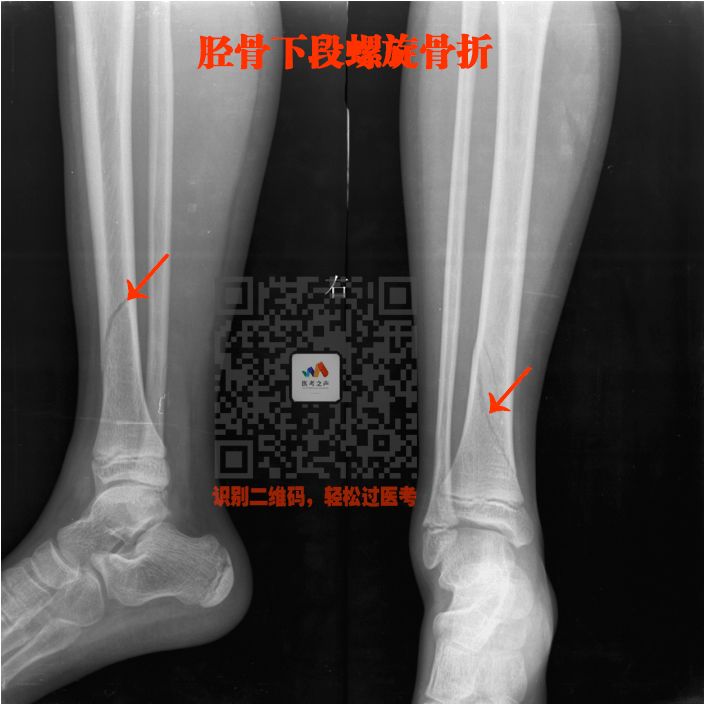

四、长骨骨折

就是四肢的长骨骨折

上肢:

肱骨、尺骨、桡骨

下肢:

股骨、股骨头、胫骨、腓骨

骨折非常简单的

这里就不讲解了,大家看片就行

看片